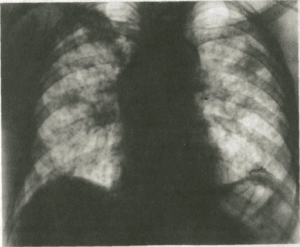

(Слева) На рентгенограмме органов грудной клетки в прямой проекции у мужчины 57 лет с гиперчувствительным пневмонитом 1-й группы («легкие любителя птиц») в обоих легких визуализируются диффузные плохо отграниченные неоднородные участки снижения пневматизации.